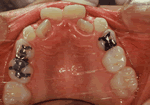

・床拡大装置について

骨格の成長に異常がない場合に使われる装置で、主に顎が小さくて歯が上手く並んでないときに用いられます。

特徴は歯を移動するだけではなく、お口のサイズを大きくすることにより、後で生えてくる歯がきれいに並ぶスペースを作るようになっています。

永久歯が生え揃ってからは顎の骨を開く(大きくするが顎の形は変わらない)優れた矯正法です。